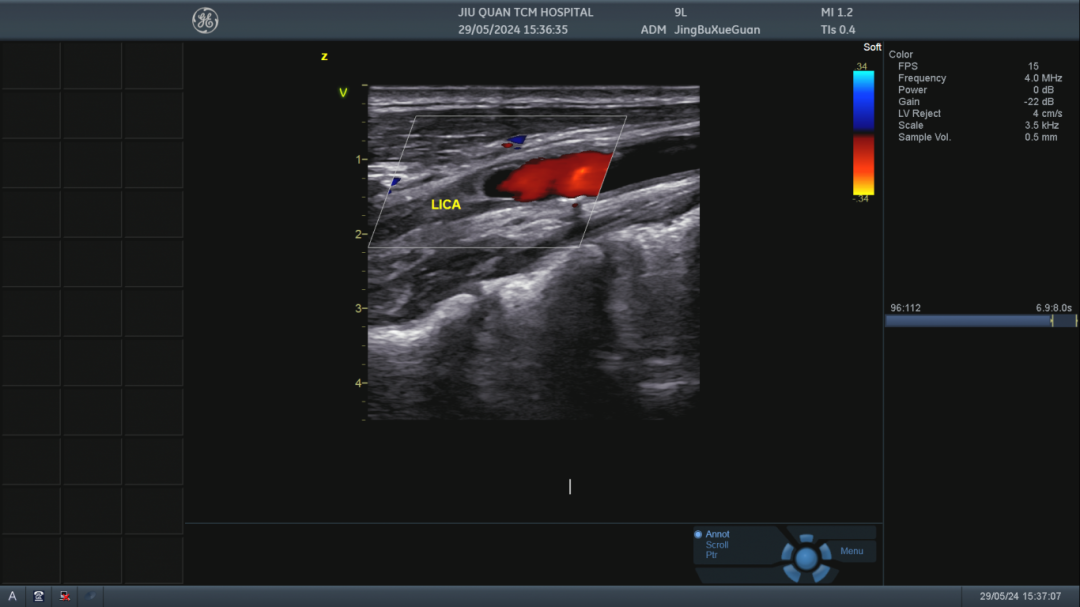

【超聲動態(tài)】 簡便卻不簡單的“腦部聽診”

經顱多普勒(TCD)利用超聲多普勒效應,以顱骨較薄部位和自然骨孔(如顳骨、枕骨大孔、眼眶等)作為檢測聲窗,對顱內動脈血流動力學進行評估,被稱為「腦部聽診器」。 ???“大爺,請放松,您的檢查結果馬上就出來了?!盩CD檢查室又響起了熟悉的對話。年高八旬的李大爺在家突感頭暈眼花,視物不清,遂由120急送我院。平素李大爺便血壓不穩(wěn),又有多年腦梗病史。這次入院后李大爺行TCD檢查示:雙側大腦中動脈輕度狹窄,左側鎖骨下動脈盜血(部分型),進一步行頸動脈超聲檢查證實左側鎖骨下動脈狹窄并盜血。因腦梗偏癱、有糖尿病史的鄭先生,入院后頸超檢查為雙側頸內動脈閉塞征,TCD檢查則更加明確判斷此患者為雙側后交通動脈開放;雙側頸內-外側枝循環(huán)開放。 自酒泉市中醫(yī)醫(yī)院成功開展經顱多普勒超聲檢查,像這樣的患者可以得到更加全面準確的相關檢查,體現(xiàn)了腦頸血管超聲檢查一體化的重要性,對患者顱外及顱內動脈血管進行系統(tǒng)全面的評估,提高檢查準確率,減少漏診和誤診,通過頸部血管超聲檢查判斷顱外血管病變的位置、狹窄或閉塞的程度,TCD檢查則可以根據(jù)血流動力學參數(shù)來判斷側枝循環(huán)開放的情況,可以通過血流頻譜及方向的改變提示鎖骨下動脈盜血程度和側枝代償情況,腦、頸動脈超聲兩者合理的結合可以為臨床醫(yī)師提供有效的信息,使臨床診斷更加明確,幫助臨床結合MRA等檢查選擇更合適的治療方案。 ??TCD可以檢測顱內前后循環(huán)血管,包括大腦前、中、后動脈,椎動脈、基底動脈、眼動脈等,由于TCD能無創(chuàng)的穿透顱骨,操作簡便,重復性好,可以對病人進行連續(xù)、長期的動態(tài)觀察。其最突出的優(yōu)勢是,可以提供核磁共振、CT等影像技術所測不到的重要血流動力學數(shù)據(jù)。因此它在評價腦血管及鑒別診斷方面有天然優(yōu)勢,為患者的有效治療提供明確方向。 現(xiàn)我院已開展TCD檢查,地址:酒泉市中醫(yī)院綜合樓二樓超聲醫(yī)學科TCD檢查室 聯(lián)系電話:0937-2669092;常溫博:18709371850